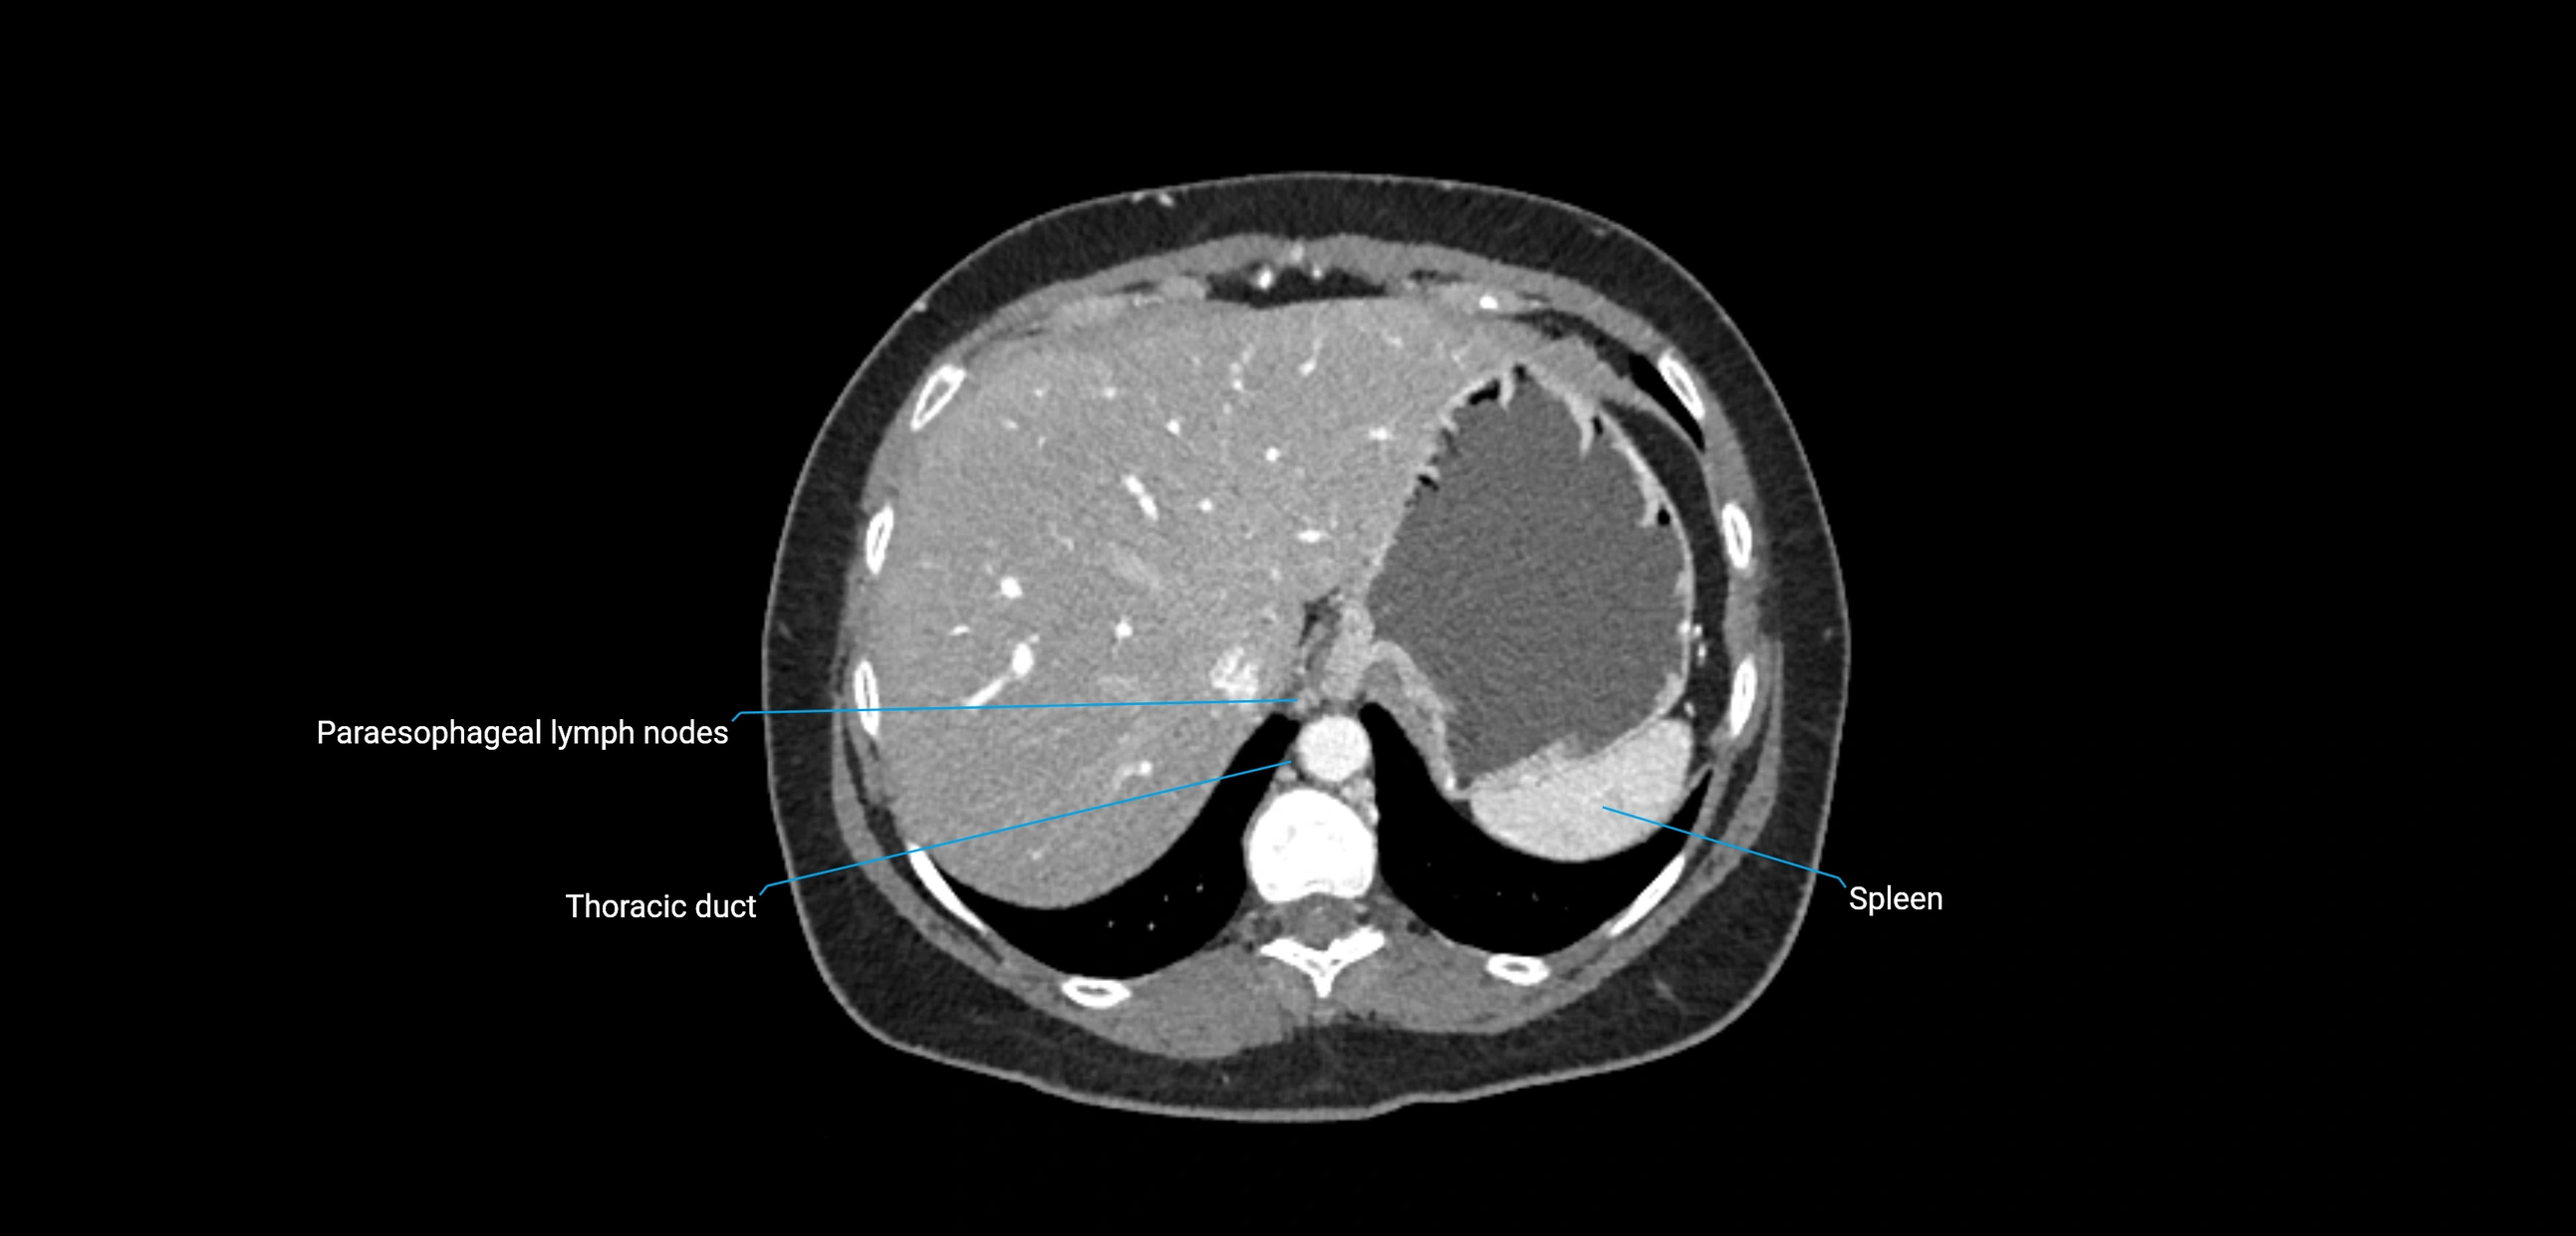

CT Appearance

CT Pre-Contrast:

• Nodes appear as soft-tissue density nodules adjacent to the aorta and IVC

• Calcification may be seen in chronic infections (e.g., tuberculosis)

CT Post-Contrast:

• Normal nodes enhance homogeneously

• Malignant nodes may show heterogeneous enhancement, central necrosis, or conglomerate formation

• Size >1 cm short axis is suspicious, though morphology and distribution are equally important

CT image

image